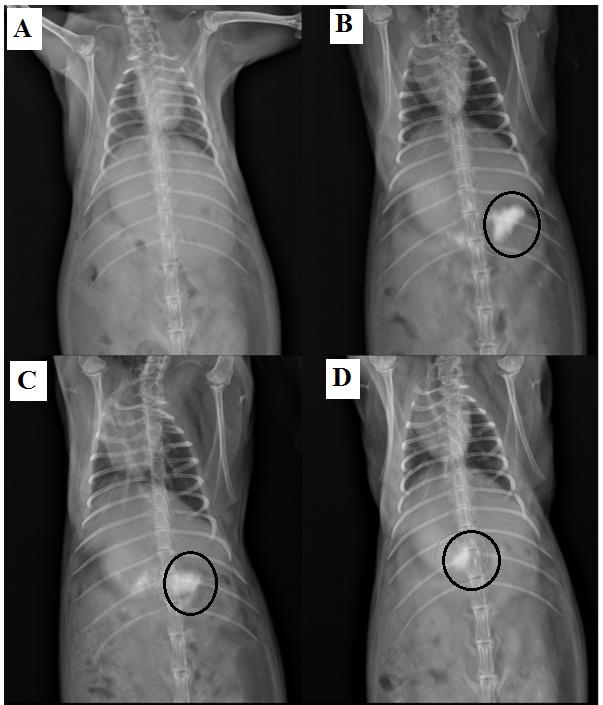

Determination of in vivo buoyancy through x-ray radio photography

For in vivo gastroretention studies conducted by using New Zealand white rabbit through x ray radio photography of this capsule [29, 30]. This experiment was carried out (X-radio imaging) according to Institutional Animal Ethics Committee (Registration no-PCP/IAEC/2023/JAN/20) by the scrutiny of Committee for the purpose of control and supervision of experiment on animal (Registration no-1698/Re/S/13/CPCSEA). For this experiment, we use 2.75±0.25 Kg weight male rabbits (from animal house of Patel College of Pharmacy) the rabbit was taken in suitable room by supplying food and water to adopt this environment. Then this rabbit holds overnight (encaged) without food before the experiments. Then conduct the experiment from early morning 6 pm to evening 6pm for completion and minimize the suffering of animal only by supplying sufficient water. Here the formulation MC4 will replace drug to BaSo4 and introduced in rabbit mouth with the help of tube flushing water carefully. Then x ray photography of gastric region in rabbit was capture at 3, 6 and 12 h time intervals [16, 29, 30].

In vivo buoyancy through x ray radio photography

For investigation of in vivo gastroretention of these metformin HBS capsules replace the drug metformin with barium sulfate by addition of MMMCH and XG to conducted X-ray radio photography by taking New Zealand adult male white rabbit [16, 29, 30]. The X-ray radio images of different time interval represented in fig. 5. It is clearly seen that the position of HBS capsules after oral administration in the gastric region or upper part of the intestine through X-ray images after 1h, 3h, 6h even 12 h of the oral administration as compare to before administration. However this study (x-ray images) clearly stated that in vivo gastroretention of these formulated HBS capsule in gastric region for a prolong periods of time will be demonstrated.

Fig. 5: In vivo X ray images of capsule in gastric region of rabbit

From this research work it was concluded that the formulation of stomach-specific HBS capsule of metformin prepared by physical blending of two opposite charge hydrophilic gel-forming colloidal polymer, namely cationic MMMCH and anionic XG (formation of electrolyte complex) help to sustain the release of drug. All these formulation showing great sustain drug release (in vitro) in gastric content (pH:-1.2) over more than 12 h, although the MC4 showing best sustain among this. Also in vitro buoyancy study showing all formulations specially MC4 will float more than 12 h in gastric content (pH:-1.2). In X-ray radio images of rabbit also demonstrated the (in vivo) gastroretention of floating HBS capsules for a prolong periods of time when administrated by replacing the drug with barium sulfate by addition of MMMCH and XG. So, these type HBS capsules of another drug with MMMCH and XG are also elegant for gastroretentive drug delivery system for their easy, negligible interaction, economical and sustain release for a prolong periods of time.